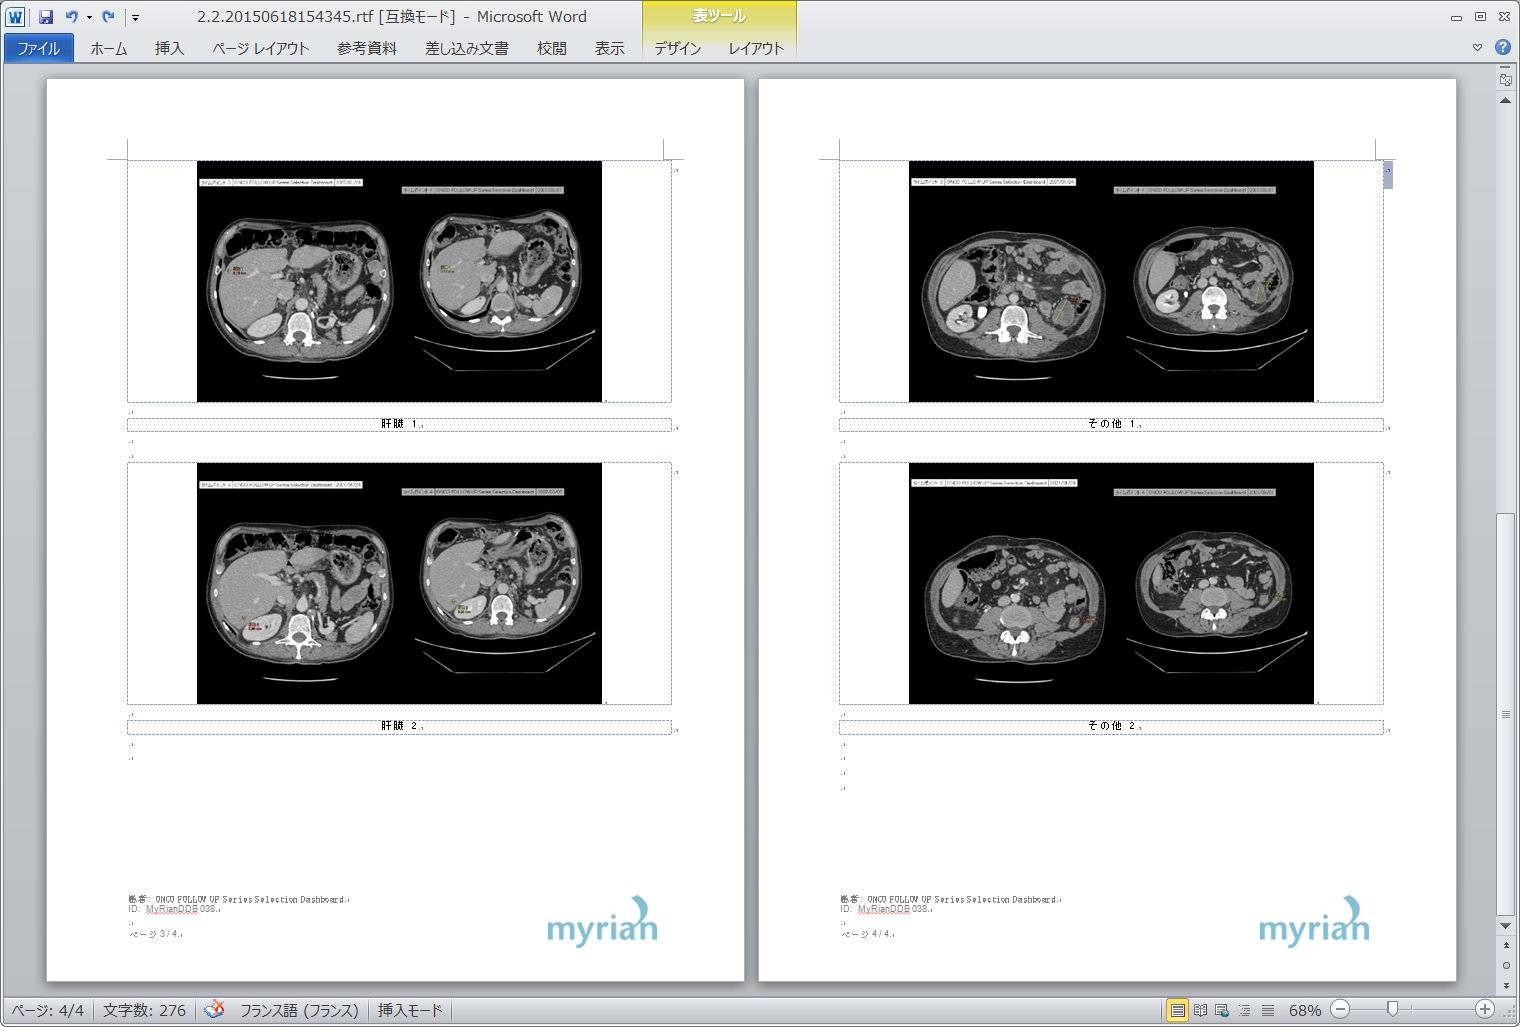

| 5.自動作成レポート |

|---|

|

|